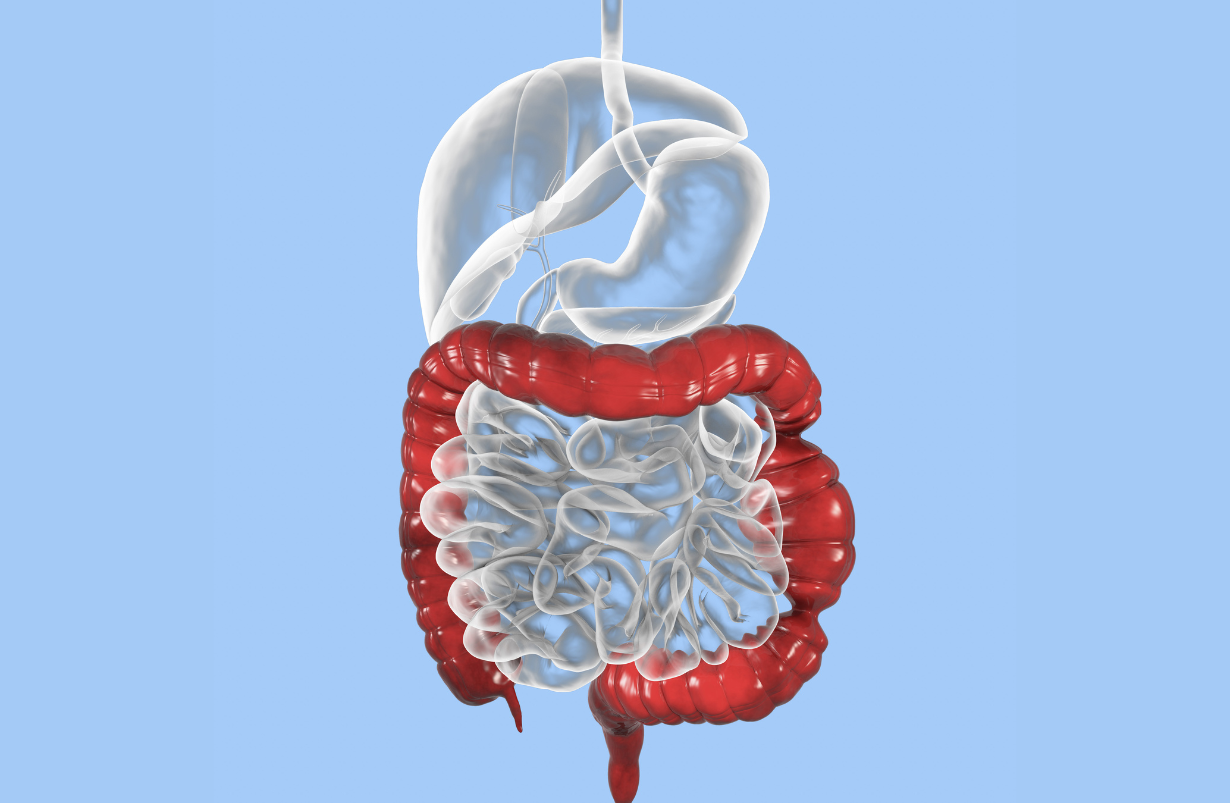

Irritable Bowel Syndrome

Irritable bowel syndrome (IBS) is said to affect 14% of adolescents, (where it frequently begins) and millions of adults in the United States. It is characterized by abdominal pain, cramping, explosive diarrhea, and other gastrointestinal abnormalities such as white or clear mucus per rectum, constipation, heartburn, bloating, nausea, and vomiting, poor libido, urinary frequency and intensifying of symptoms premenstrually. It is not an inflammatory condition. Symptoms maybe brought on by stress. It is unusual for IBS to appear first in adulthood, and although it is possible, these symptoms appearing first in adults may often be due to other, more organic causes. A general yoga regimen is reported to help quite a bit, as is mindfulness training. Schumann D, Anheyer D, Lauche R, Dobos G Langhorst J, Cramer H. Effect of Yoga in the Therapy of Irritable Bowel Syndrome: A Systematic Review. Clin Gastroenterol Hepatol. 2016 Dec;14(12):1720-1731. doi: 10.1016/j.cgh.2016.04.026. Epub 2016 Apr 22.PMID: 27112106 DOI: 10.1016/j.cgh.2016.04.026